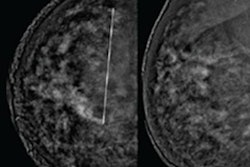

Contrast mammo vs. breast MRI

Meanwhile, be sure to visit our Women's Imaging Community for an article on a research study that compared contrast mammography to breast MRI to assess response to treatment for breast cancer.